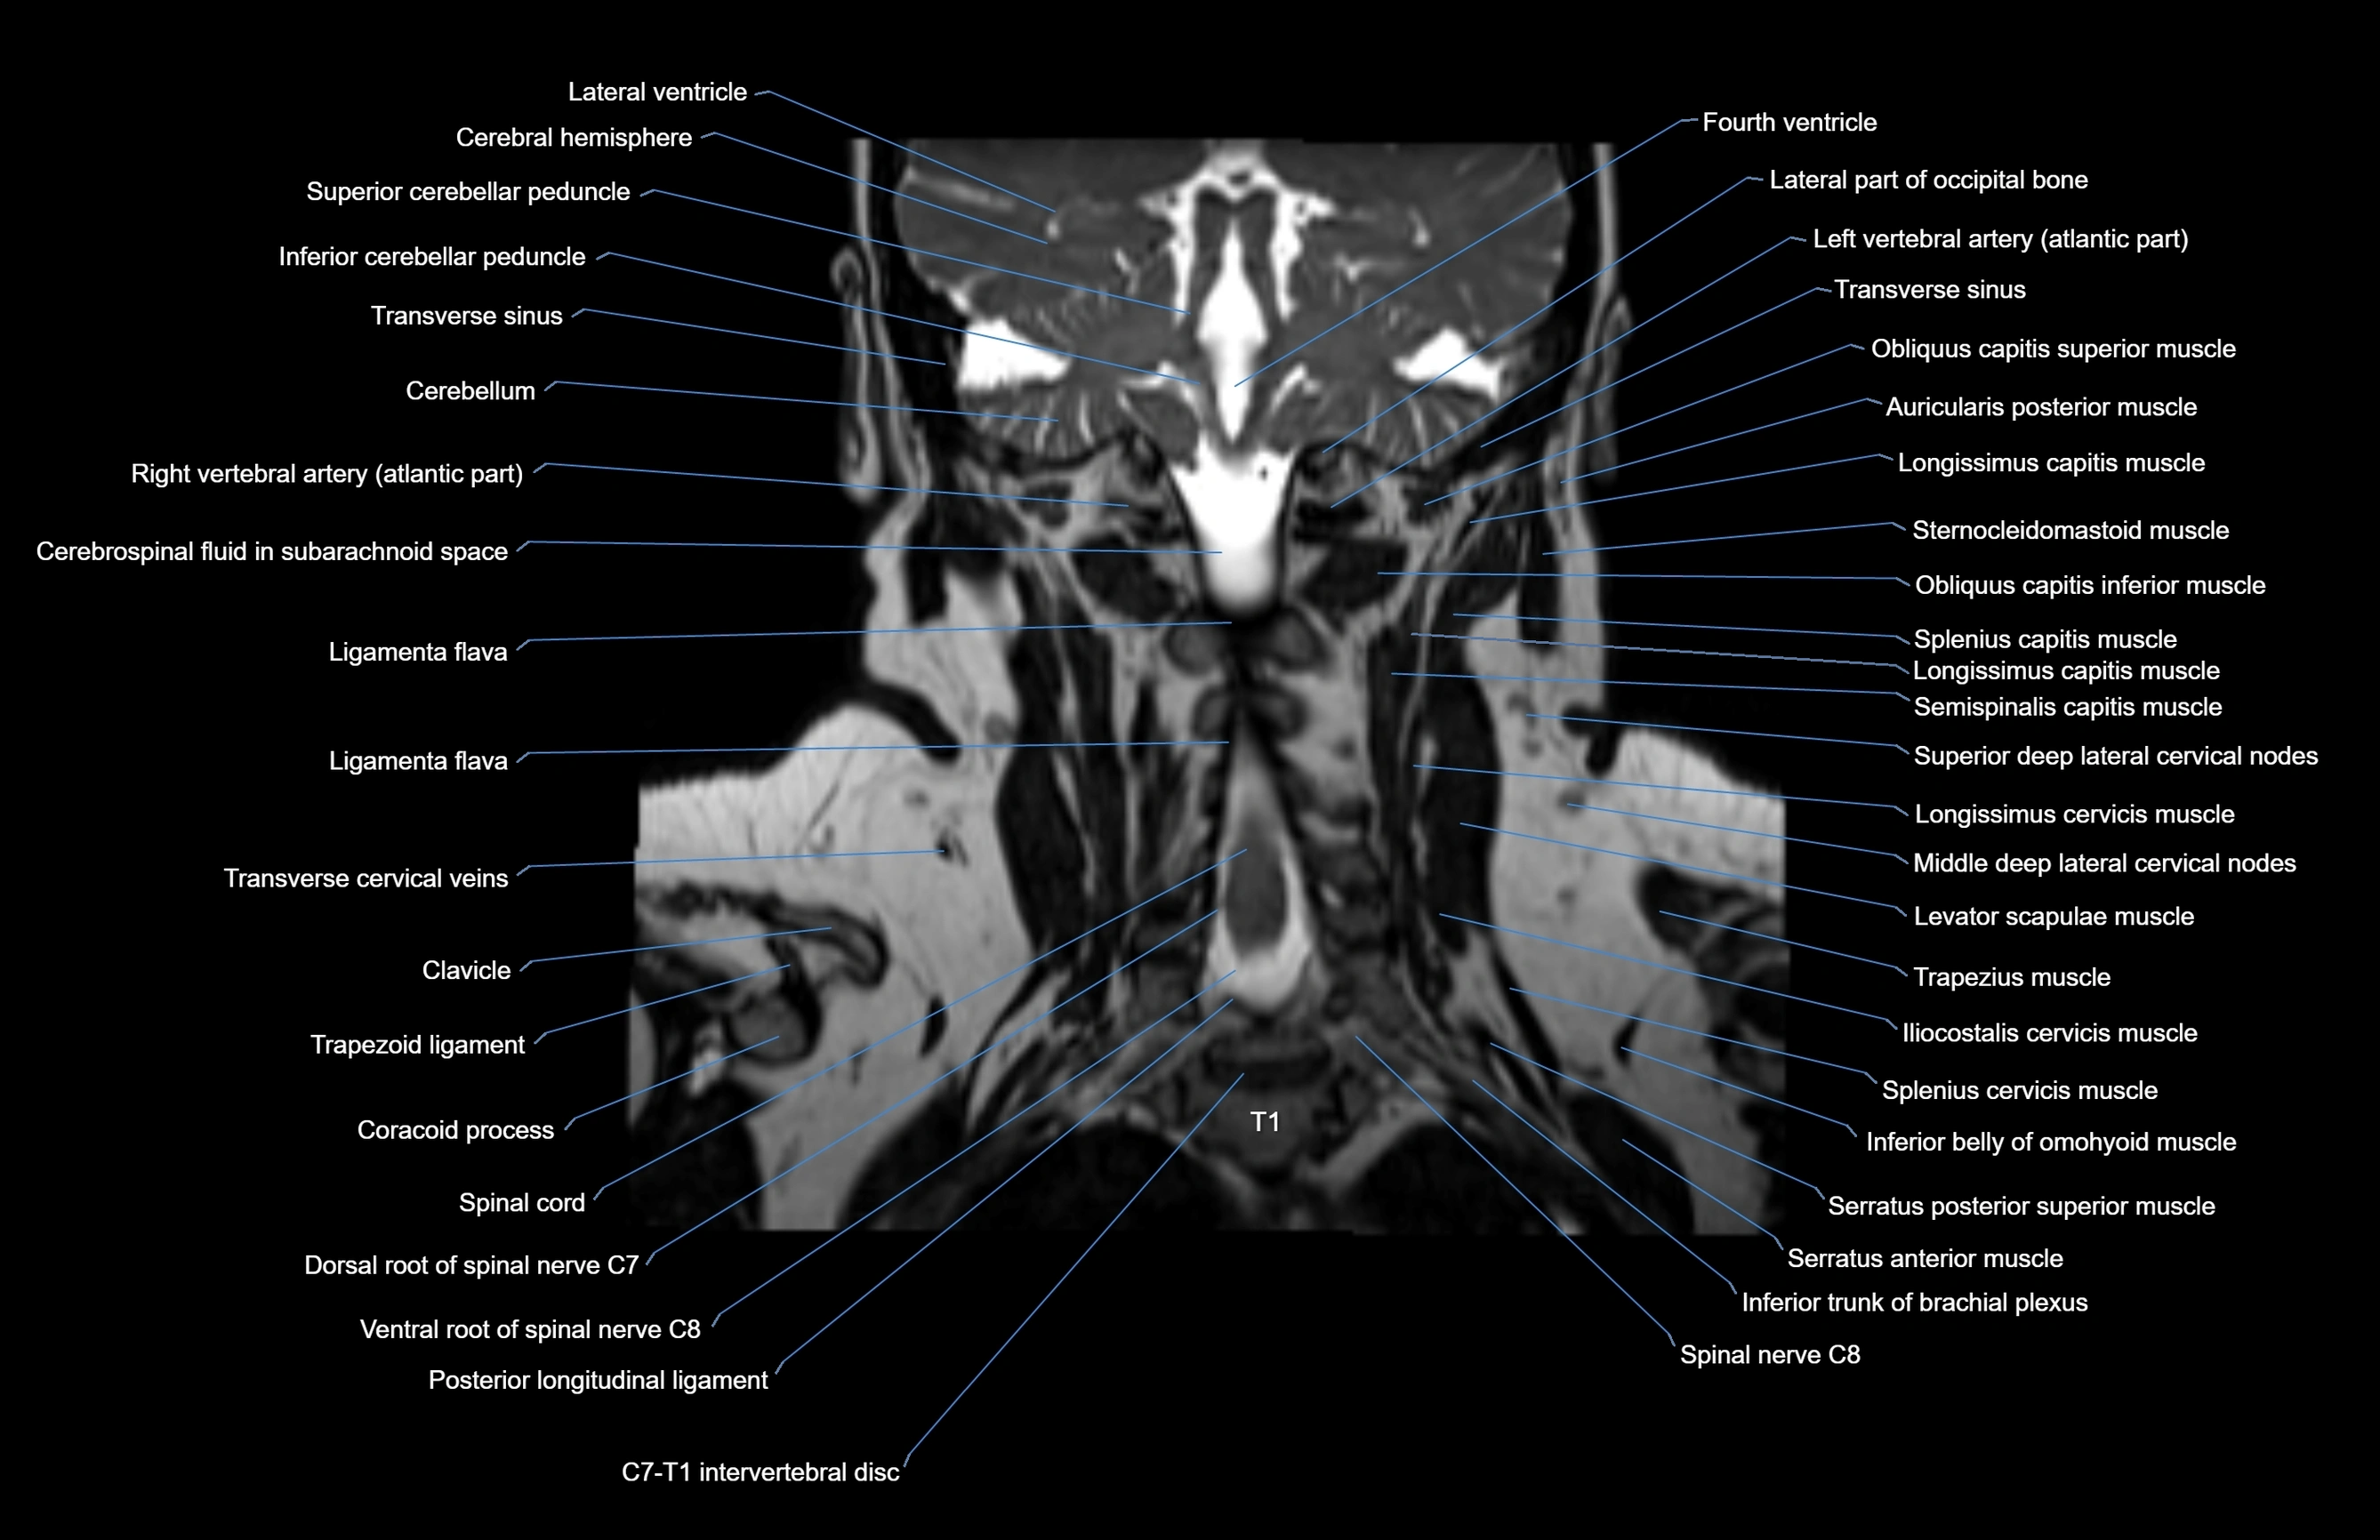

- Inferior cerebellar peduncle

- Left vertebral artery

- Left vertebral artery (atlantic part)

- Ligamenta flava (Ligamentum flavum)

- Posterior longitudinal ligament

- Right vertebral artery (atlantic part)

- Spinal cord

- Ventral root of spinal nerve